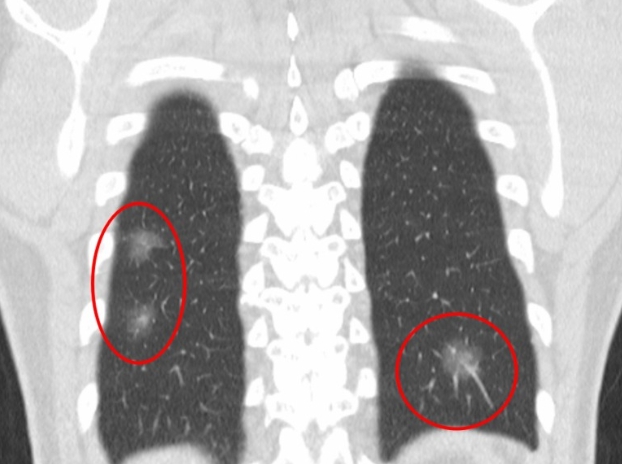

폐 편평세포암은 폐암의 한 유형으로, 주로 흡연과 관련이 있습니다. 기침이 3주 이상 지속되거나 피 섞인 가래, 숨이 차는 증상이 있으면 검사를 받아야 합니다. 흡연자는 비흡연자보다 편평세포암 발생 위험이 몇 배나 높습니다. 금연은 가장 강력한 예방책이며, 폐 건강을 지키는 가장 직접적인 방법입니다.

진단은 흉부 X선, CT, 기관지 내시경, 조직검사로 이뤄집니다. 치료는 수술, 방사선, 항암치료, 면역치료가 병합됩니다. 최근에는 맞춤형 치료제가 도입되어 생존율이 향상되고 있습니다.